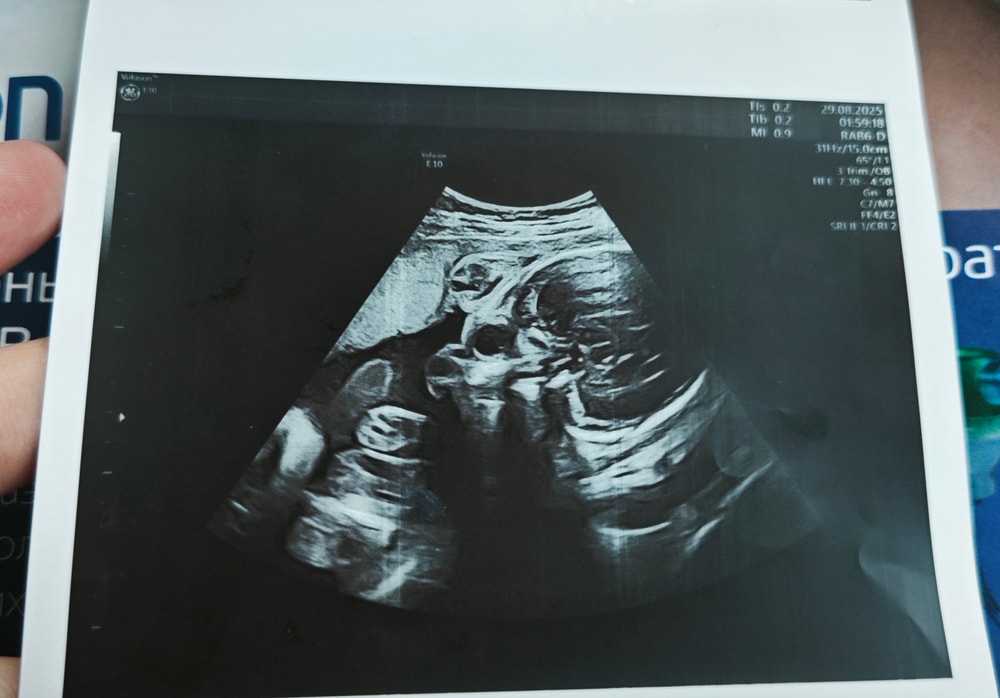

Сходила в частную клинику на УЗИ в 28 недель, сказали, что всё хорошо ттт, и дали фото. И вот когда я уже вышла с клиники и увидела фото, я вообще ничего не поняла. Это вроде голова, но вообще непонятно что где и выглядит жутковато...

Может тут кто-то разбирается или понимает что где на этих фото?

Я понимаю, что это череп. Но, с какого ракурса понять не могу🤣

Голова и ручки около лица. Голова у них на узи со всем содержимым видна🤣, потому и жутковато выглядит🤣🤣🤣